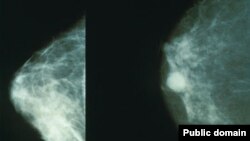

‌ هغه د ناروغۍ د علاماتو او علاج په اړه وايي‌: "پکار ده چې لوموړی خپل ځان وګورو. که داسې څه غوټه وي،‌ پړڅوپ وي یا دانه وي،‌ په ترخونو کې،‌ یا په دې ځای کې ورته څه غیرعادي ښکاره شي‌، که د سینې نه نو وینه راوتل شروع شي‌ نو دا ټول علامات دي‌، یا په پوست کې څه بدلون راشي او یا په سینه کې څه بدلون راشي نو هرې ښځې ته پکار دي چې خپل چیک اپ وکړي.‌ بهترینه خبره دا ده چې ډاکټر ته دې ورشي، هلته یو خاص قسم میموګرافي ایکس رې کېږي چې وړه نه وړه دانه هم مالوموي.‌ په څلورم سټیج کې د دې سرطان علاج نه کېږي خو په اولني‌او دویم پړاو کې د دې علاج ممکن دی."